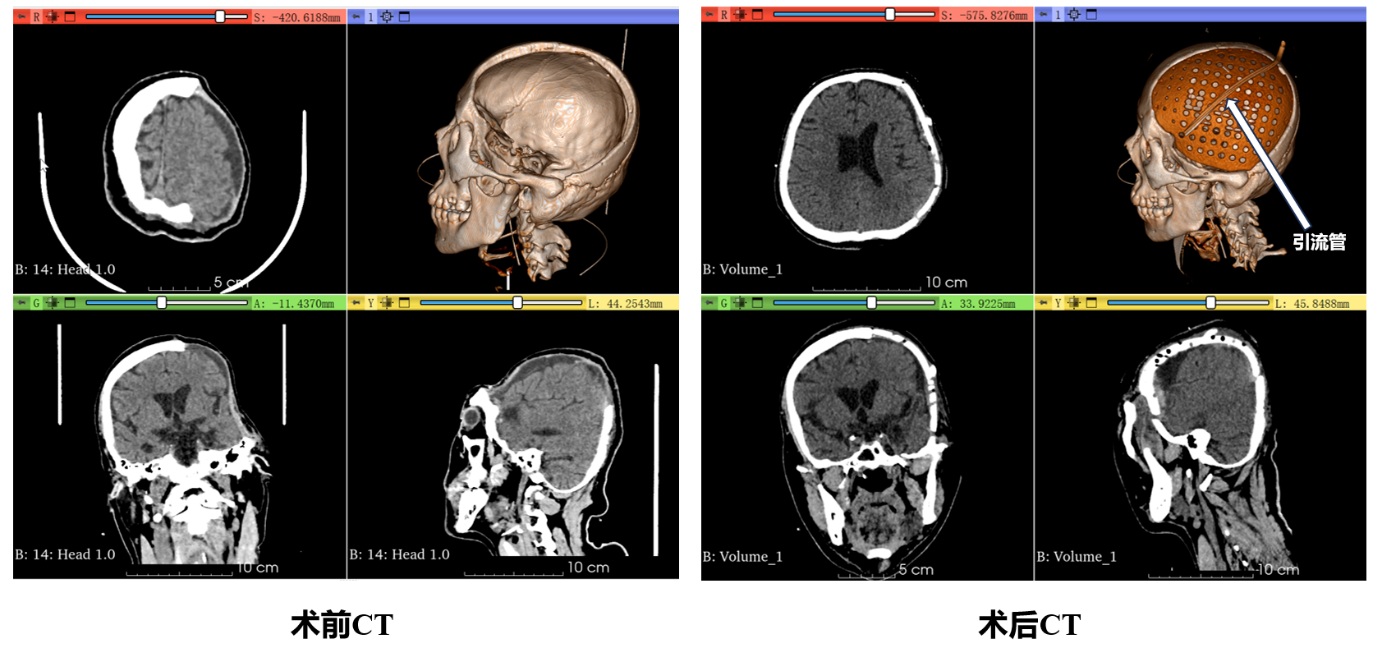

术前,团队通过高精度CT扫描获取徐先生缺损的颅骨数据,精准打印出专属修补支架。术中,医护人员精细操作,将支架精准植入缺损处并牢固固定。术后影像学检查显示,支架位置精准,与周围骨组织贴合紧密、间隙极小,皮下积液相较术前明显减少,手术效果达到预期。经过医护团队的精心护理,徐先生意识状态明显好转,头部外观也恢复了正常,家属对治疗效果十分满意。